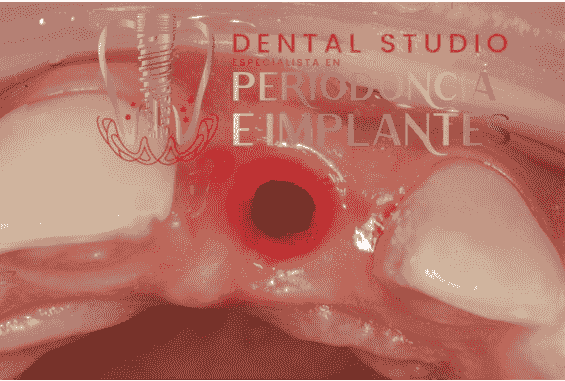

Implantes Dentales

Realizamos la colocación de implantes dentales con planificación computarizada, asegurando una integración óptima y duradera en tu boca, así como un seguimiento continuo para prevenir complicaciones.